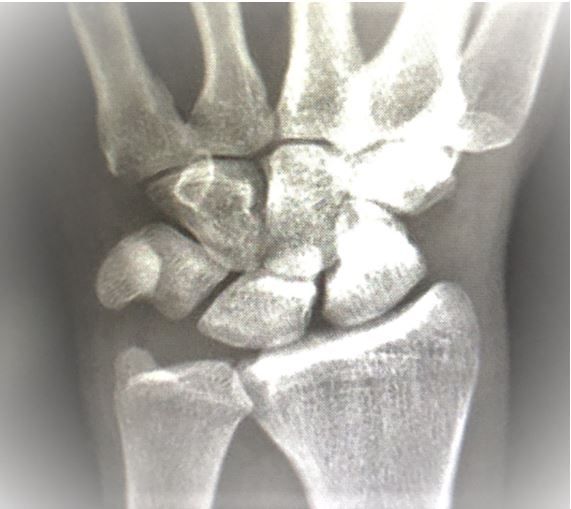

A skateboarding accident brings a man in his 30s to the ED complaining of wrist pain. Can you make the diagnosis based on the x-ray?

A man in his 30s comes to the emergency department (ED) for wrist pain after a fall while skateboarding today. He denies any elbow, shoulder, head, neck or back pain or other complaints.

Physical examination is otherwise normal except for diffuse wrist tenderness, more on the radial side without obvious deformity. His distal neurovascular and tendon exam is intact although limited by pain. Skin is intact and compartments are soft.

Relevant test results: Imaging, x-ray